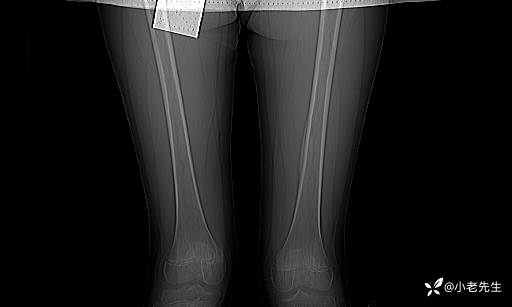

1月3日DR